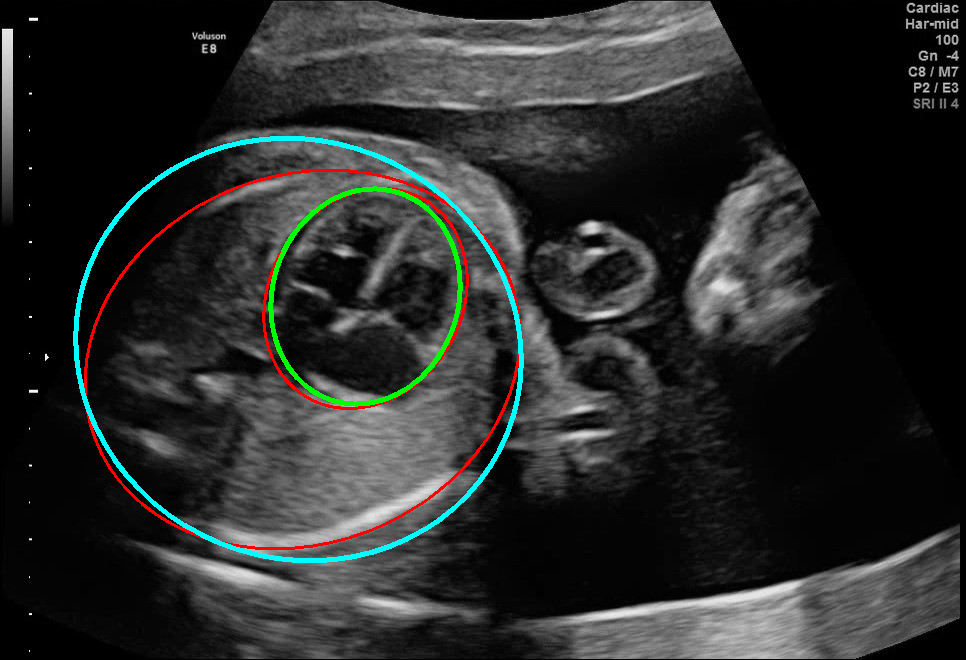

Visualization results of different methods.

Although the segmentation model trained on the fetal ultrasound dataset achieves a relative high average dice scores averaging over 0.9, the fitted ellipse highly depends on the segmentation results. As shown in the middle row of Fig. 2, the segment-based ellipse-fit method performs well when the image quality is good (first row), but the performance degrades when the segmentation is affected by image artifacts such as the acoustic shadowing (second and third row). Our proposed method is more robust to image quality and shadows. We also tried to compare to the GPN [9] with their open source code on our dataset, however, the results are not comparable to ours and those presented in Table. 1. It is difficult to conclude whether it is caused by the network itself or the training strategies. We, therefore, did not include the comparative results in this work.

As shown in Fig. 3 , both the proposed ellipse regression loss and IoU loss are necessary for ellipse detection. If the EllipseNet only supervised by IoU loss (first column), the model fails to optimize the major and minor axis separately, and the predicted ellipses degenerate into circles like the CircleNet. It is clear that the supervision of IoU loss can help to improve the prediction of location and shape (first and second row) and to correct the angle (last row).